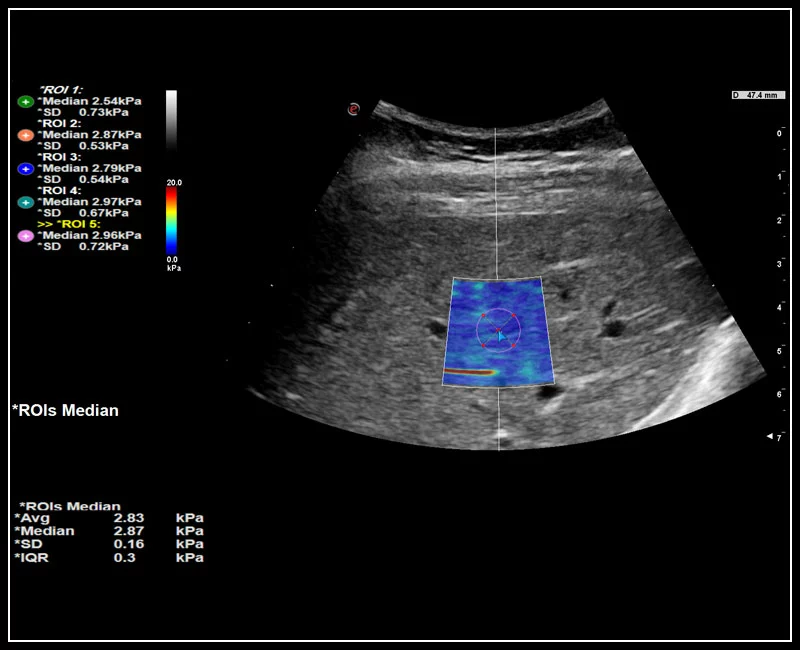

MyLab™9 Platform - QElaXto point Shearwave Elastography in liver

MyLab™9 Platform - QElaXto point Shearwave Elastography in liver

MyLab™9 Platform - QElaXto 2D shearwave elastography in liver

MyLab™9 Platform - QElaXto 2D shearwave elastography in liver

MyLab™C30 - QElaxto 2D liver

MyLab™C30 - QElaxto 2D liver

MyLab™X8 Platform - Stiffness quantification with Q-ElaXto

MyLab™X8 Platform - Stiffness quantification with Q-ElaXto